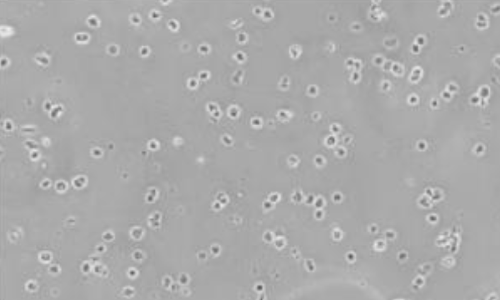

▲人肺 FFPE 样本 |